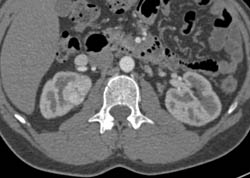

Renal Cell Carcinoma